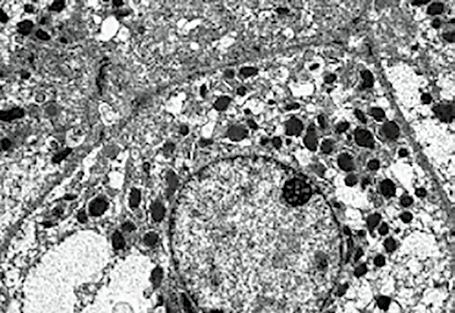

Bylo již uvedeno, že už dříve byl objeven jaterní lobulus, jehož koncepci detailně propracoval Kiernan v 19. století. Nové, soudobé pojetí lalůčku zavedl Rappaport, který rozdělil lalůček na tři zóny podle jejich vztahu k portálnímu prostoru. Jaterní architekturu objasnil v roce 1949 Elias. Podle jeho koncepce jsou játra složena z jednovrstevných buněčných plátů a trámců, které probíhají a ohýbají se ve všech směrech a vzájemně se prostupují tak, že vytvářejí nepravidelnou síť, která je prostoupena labyrintem lakun. Játra tak nabývají vzhledu mořské houby (obr. 1.13). Toto uspořádání je velice výhodné po stránce funkční. Elektronmikroskopické studie

Obr. 1.13 Houbovité uspořádání jaterní struktury (podle Eliase)

pak prokázaly vybavení hepatocytů různými organelami a umožnily i poznání vyvolávajících infekčních agens v jaterních buňkách.